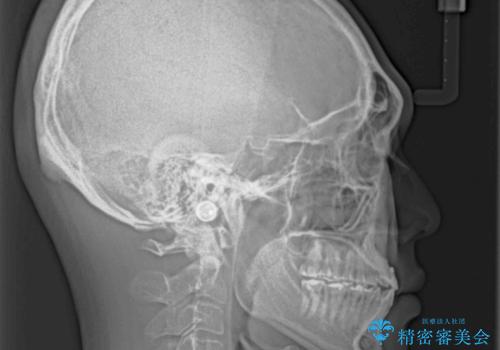

前歯のクロスバイトを改善 ワイヤー装置での非抜歯矯正

- 骨格的な咬み合わせのズレ、前歯のデコボコとクロスバイトを気にして来院された患者様です。

骨格のズレが顕著であると診断され、マウスピース矯正では奥歯の咬み合わせが整えにくいと判断し、ワイヤー装置による矯正治療を行うこととしました。

上下の叢生は速やかに改善できましたが、右側のクロスバイトの改善に1年以上の期間を要しました。